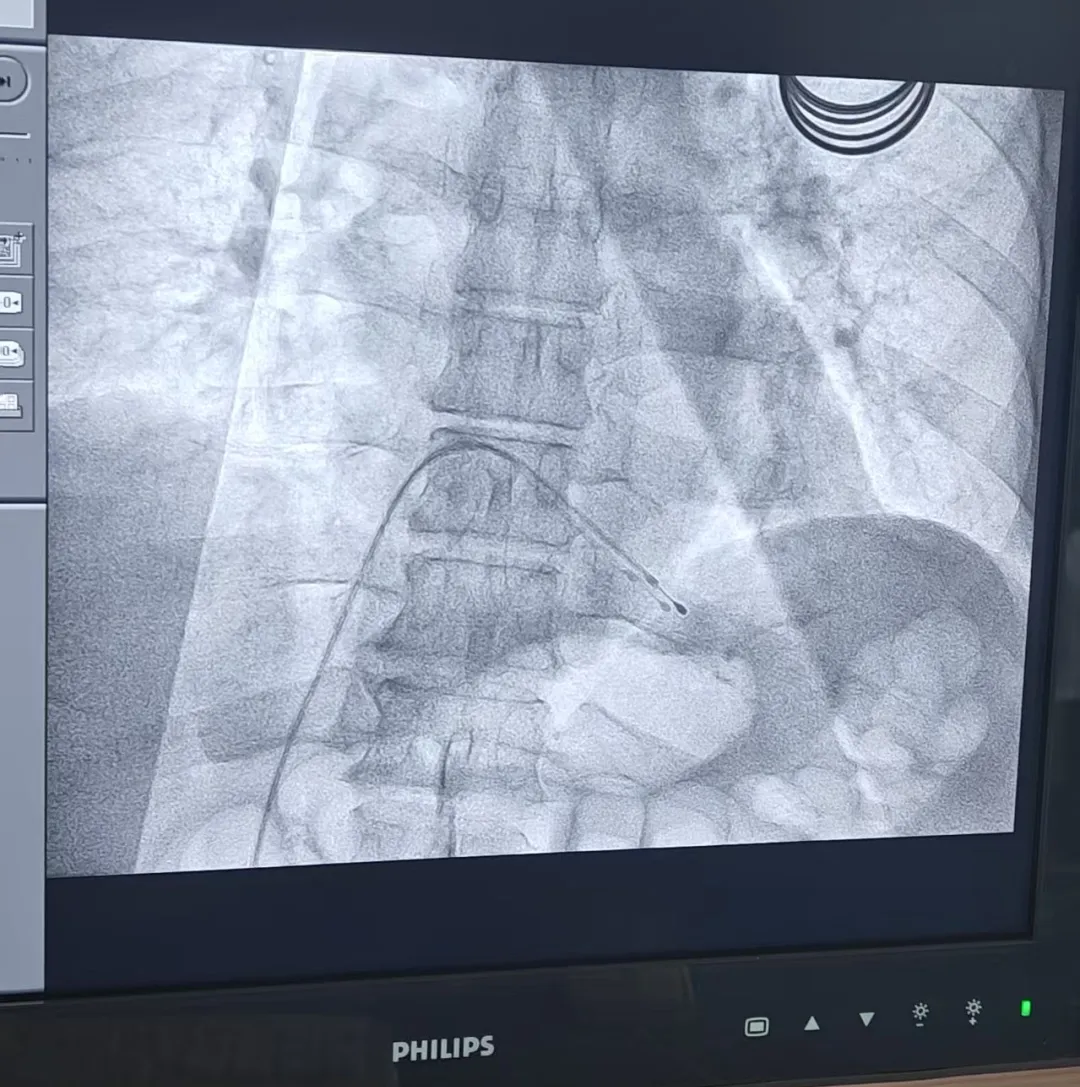

心血管内科一病区羡微微主任与

崔东吉副主任医师为患者置入临时性心脏起搏器

经过审慎评估,团队制定出精密的分步治疗方案:首先,由心血管内科一病区羡微微主任与崔东吉副主任医师“打头阵”,在介入室为患者置入临时心脏起搏器,为手术全程保驾护航,预防心跳骤停风险。随后,患者被直接转入手术室,许景伟主任与周涛副主任团队“接力”,麻醉科田燕南副主任全程守护在患者旁,一台牵动人心的腹腔镜下乙状结肠癌根治术马上开始。